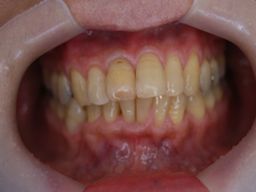

症例3

フィステル(瘻孔)があって、変色している症例。根管治療をすると、フィステルは消失。

で、漂泊してCR充填すればきれいに出来上がり。